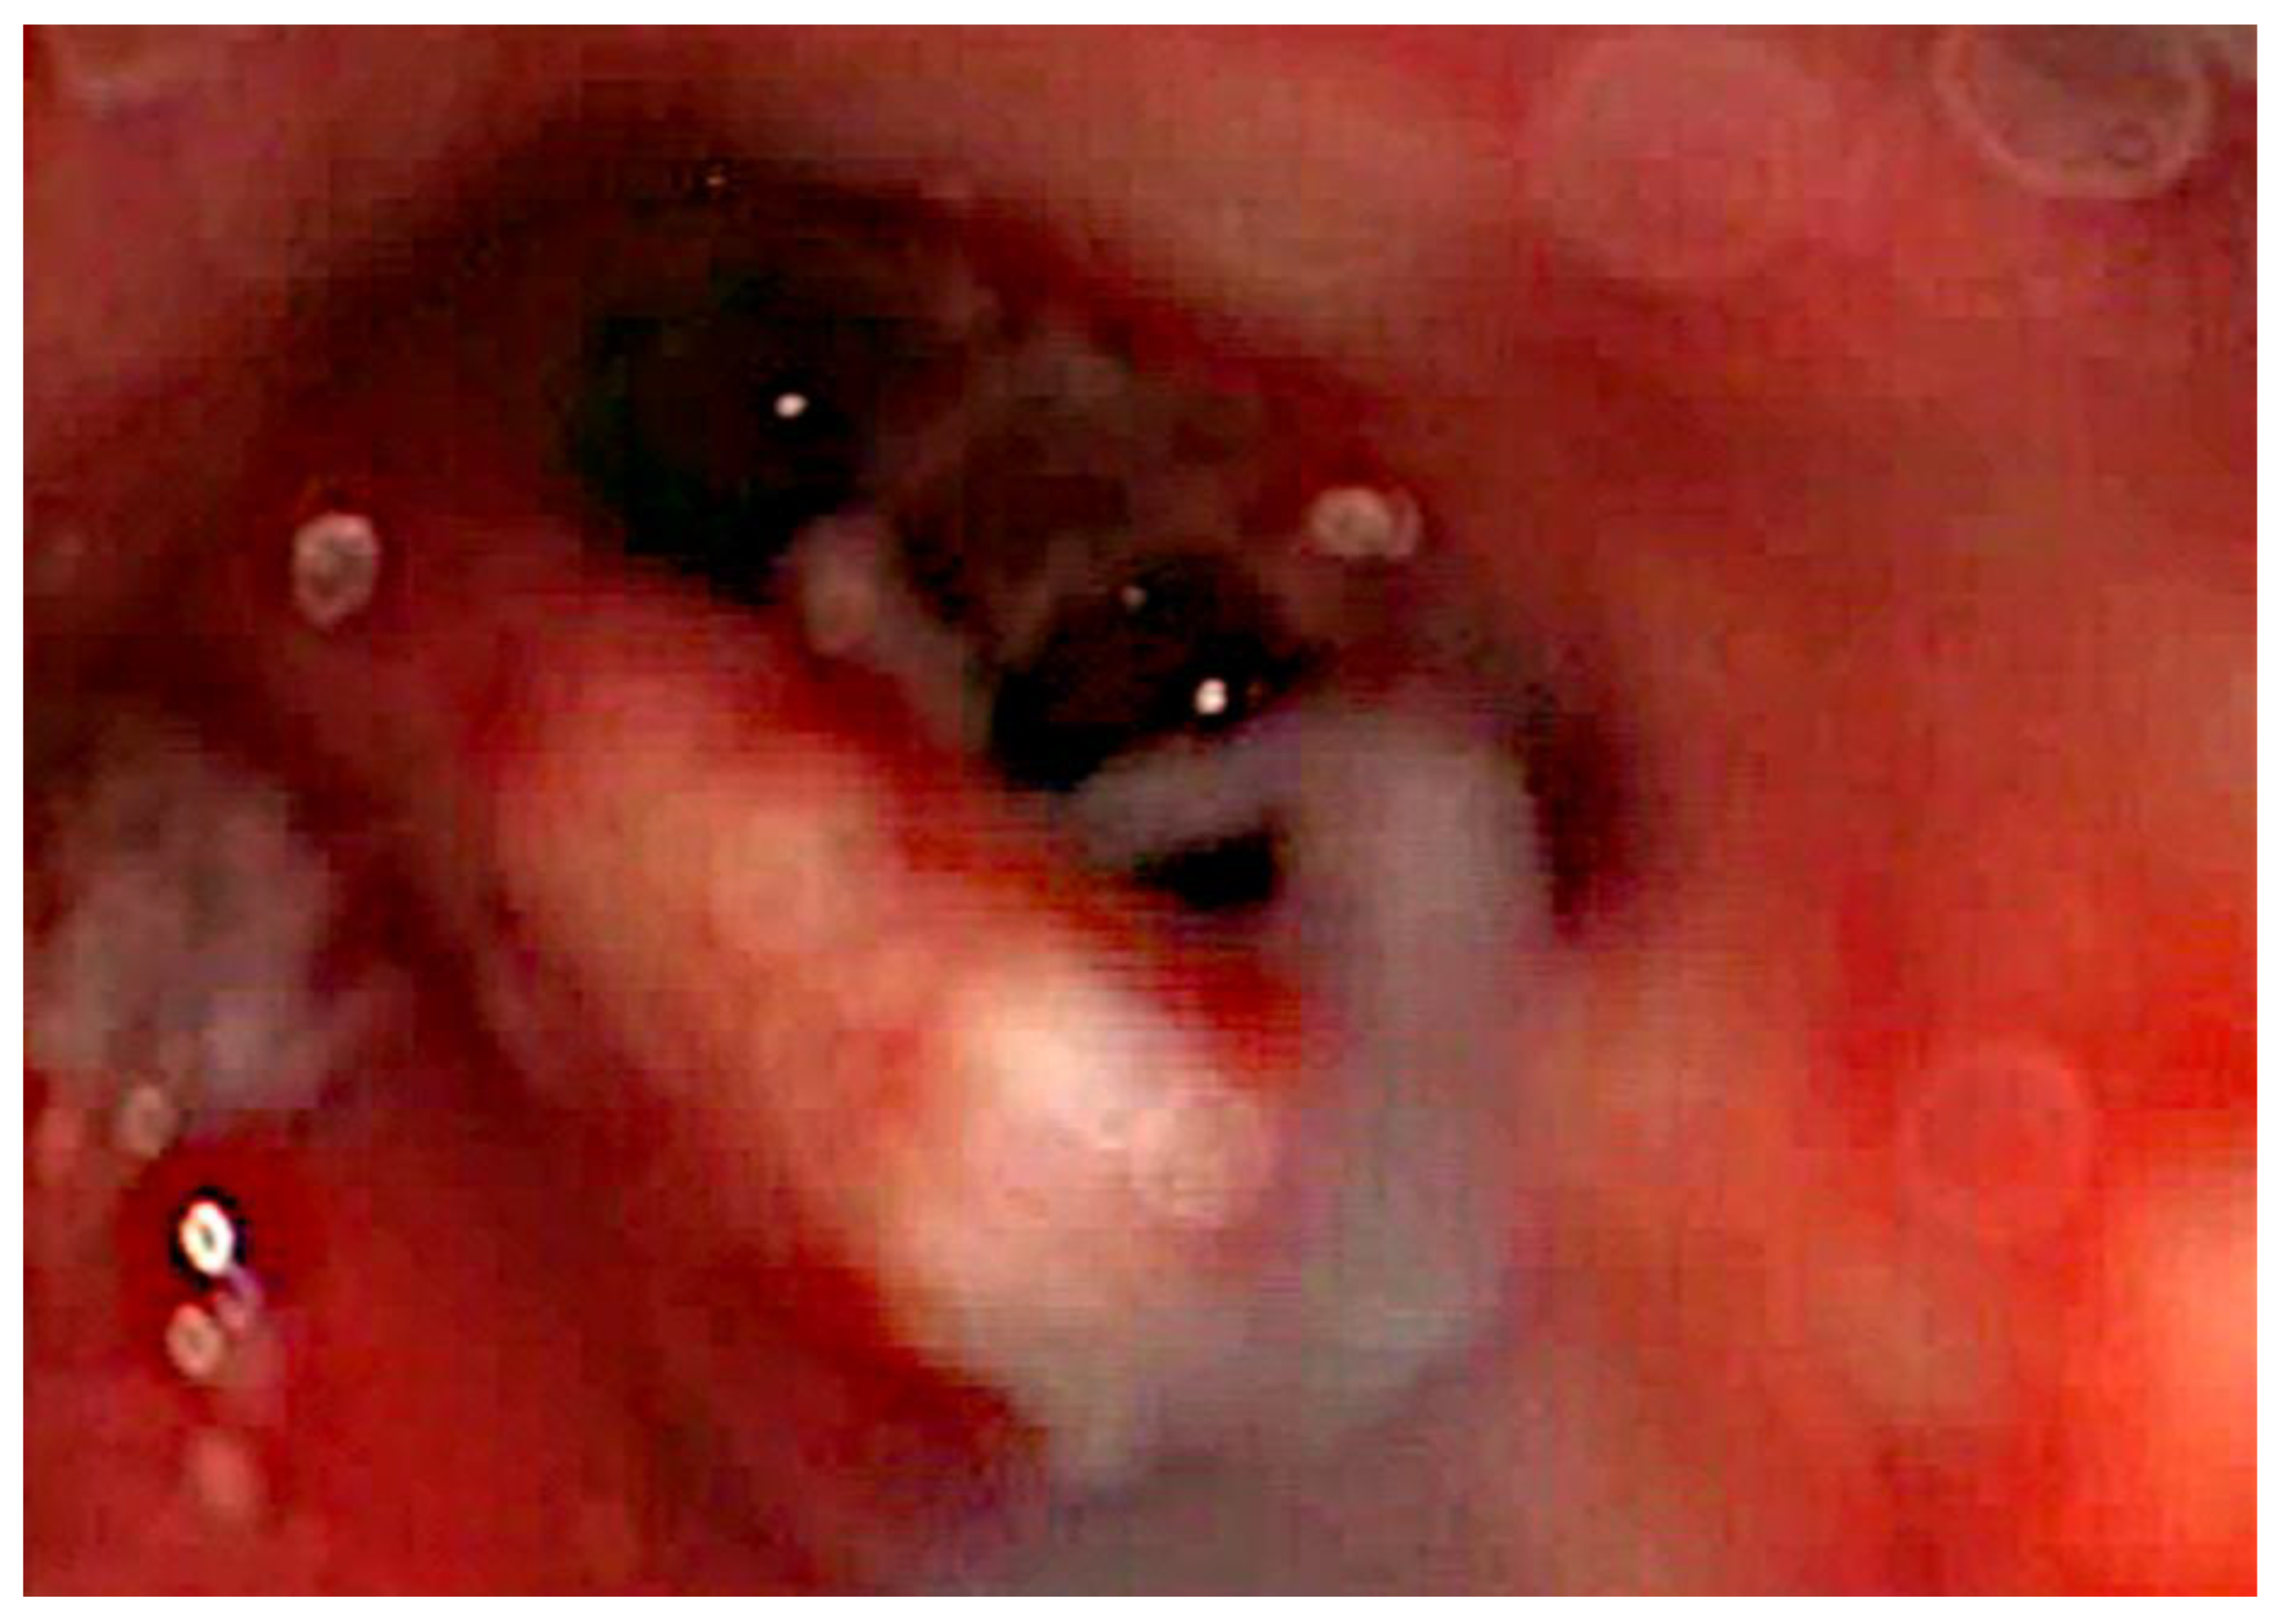

After the removal of parts of the tumor through the enlarged cochleostomy (Figure 1) the TRD was introduced (Figure 2) until the tip was visualized (Figure 3) and carefully grabbed out of the second turn access. By grabbing the tip, the device slipped into the cochleostomy and pushed parts of the tumor out of the second turn. Residual tumor parts could be detached by pipe cleaner handling (Figure 4) and sucked out (Figure 5).

Figure 1. Tumor in the scala tympani with basilar membrane and scala vestibuli.

Preprints 103791 g001